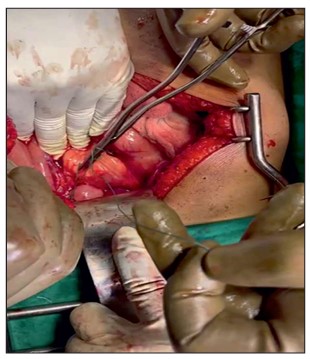

Nissens Fundoplication: A Laparoscopic Edge?

Background: Hiatal hernia often leads to gastroesophageal reflux disease (GERD), which may be refractory to medical therapy. Surgical intervention in the form of Nissens fundoplication can provide definitive relief. With advancements in minimally invasive techniques, the role of laparoscopic Nissens fundoplication is increasingly prominent. Aim: To compare the effectiveness of open versus laparoscopic Nissens fundoplication in patients with endoscopically confirmed hiatal hernia. Objectives: • Compare operative time, symptom relief, and complications in open and laparoscopic procedures. • Evaluate improvement using De-Meester Johnson reflux score. Material: A prospective study involving 38 patients (18-60 years) at a tertiary care hospital over 18 months (Sep 2022 - Mar 2024). Patients were randomized into two equal groups for open or laparoscopic Nissens fundoplication. Results: Both groups showed significant symptomatic improvement. Laparoscopic surgery had a longer operative time (135 vs 110 minutes) but fewer complications and better De-Meester scores Post-operatively. Statistically significant improvement in heartburn, regurgitation, and dysphagia was observed, especially by Postoperative day 7. Conclusion: Laparoscopic Nissens fundoplication is as effective as open surgery in relieving GERD symptoms, with additional benefits of fewer complications and faster recovery, despite longer operative duration.